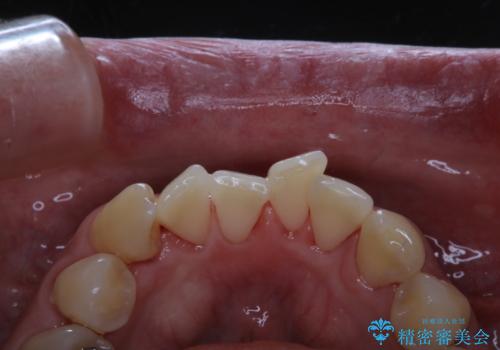

- マスクの着用により、口臭が気になるためクリーニングをしてほしいとのことでした。PMTC60分コースを行いました。

PMTCとはProfessinnal Mechanical Tooth Cleaning・専門器具による歯の機械的な清掃です。

バイオフィルム(細菌の塊)を破壊し、歯の表面をツルツルにすることでお口の中の細菌数を減らし歯周病のリスクが定着するのを防ぎます。更に、歯に新しい汚れがつきにくい状態になります。